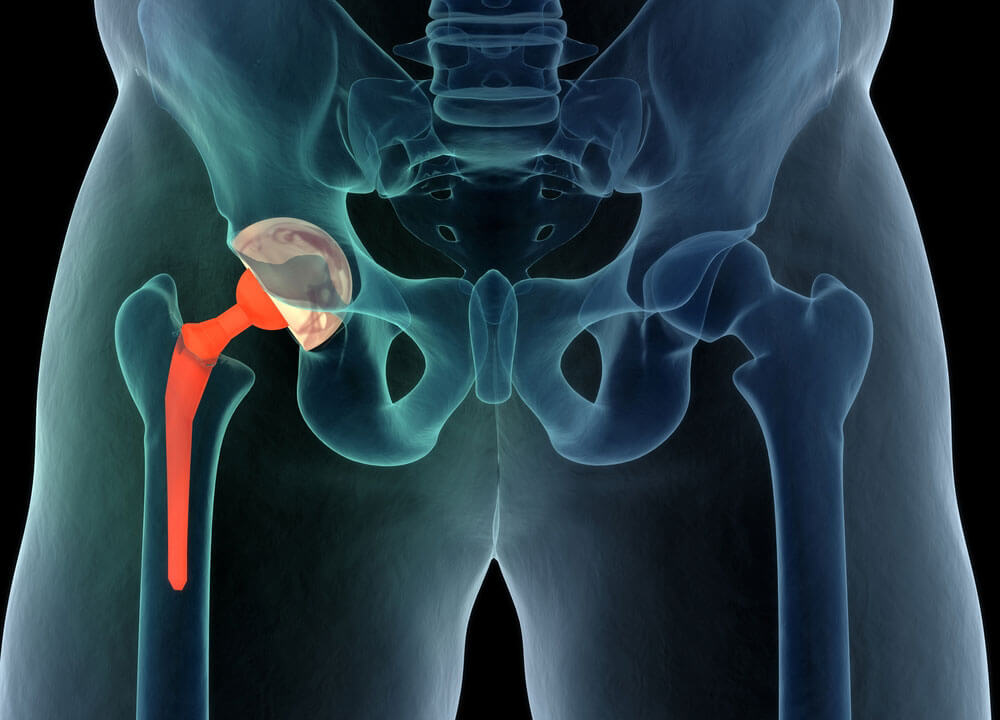

Total joint replacement is a surgical procedure in which parts of an arthritic or damaged joint are removed and replaced with a metal, plastic or ceramic device called a prosthesis. The prosthesis is designed to replicate the movement of a normal, healthy joint.

Hip and knee replacements are the most commonly performed joint replacements, but replacement surgery can be performed on other joints, as well, including the ankle, wrist, shoulder, and elbow.

Total Hip Replacement

Whether you have just begun exploring treatment options or have already decided to undergo hip replacement surgery, this information will help you understand the benefits and limitations of total hip replacement. This article describes how a normal hip works, the causes of hip pain, what to expect from hip replacement surgery, and what exercises and activities will help restore your mobility and strength, and enable you to return to everyday activities.

If your hip has been damaged by arthritis, a fracture, or other conditions, common activities such as walking or getting in and out of a chair may be painful and difficult. Your hip may be stiff, and it may be hard to put on your shoes and socks. You may even feel uncomfortable while resting.